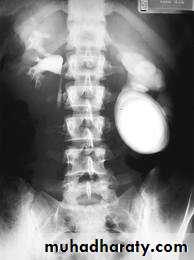

Schistosomiasis

Infestation by s.hematobiumCalcification is most important feature, mainly in bladder & lower ureters , but may involve whole ureters .

In early stage inflammation may cause cobble stone appearance.

Bladder capacity not affected.

Ddx of bladder calcification :

1. schistosomiasis .2. tumor , TB …